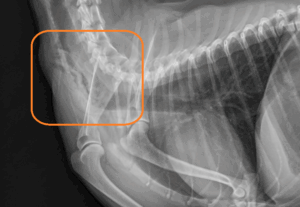

- Het is belangrijk dat een röntgenfoto gemaakt wordt om de diagnose met zekerheid te stellen, ander probleem wat dezelfde klachten kan geven is namelijk een maagtorsie.

Slokdarmobstructie in de hals – hieronder beelden van de endoscopie.